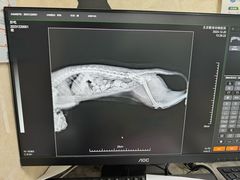

• 酷宠动物医院(天通西苑店)

• 全部图片

• 全部图片»

• 商户官方图片»